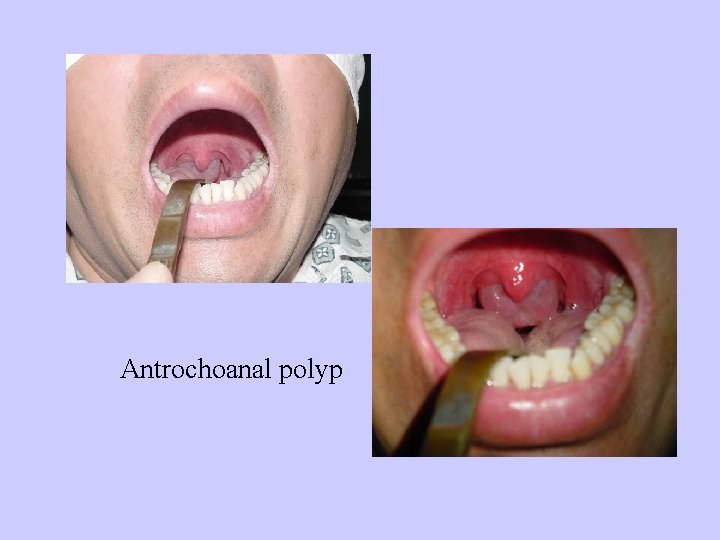

Antrochoanal polyp